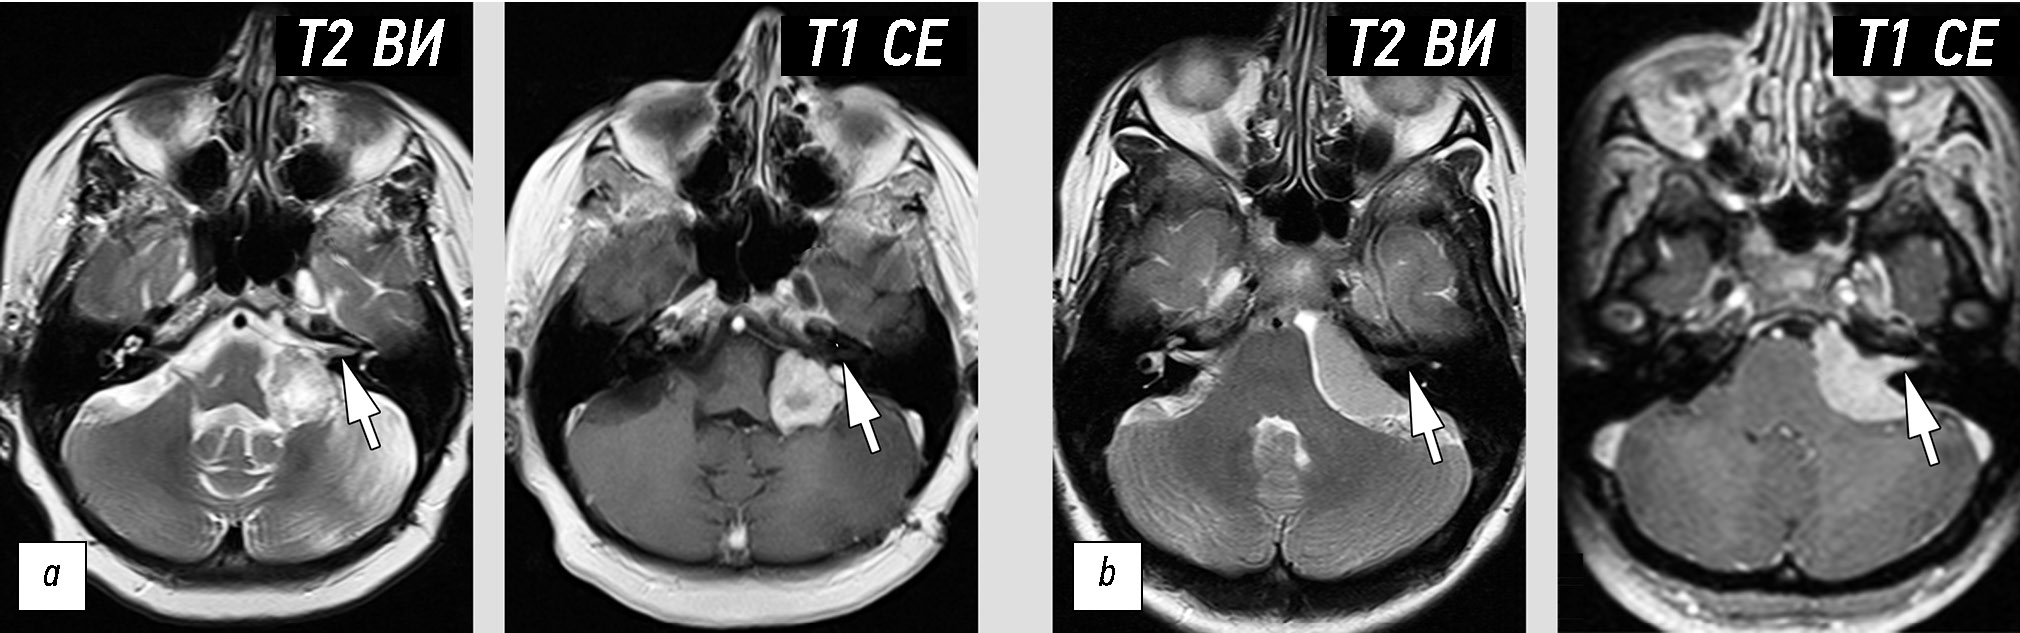

Одним из признаков, позволяющим дифференцировать опухоль мостомозжечкового угла от невриномы и менингиомы, является наличие взаимосвязи образования с черепными нервами или мозговой оболочкой. Два следующих примера демонстрируют, что в ряде случаев однозначно установить эту взаимосвязь бывает затруднительно. Дополнительную сложность создаёт и тот факт, что любые образования данной локализации будут иметь схожие клинические проявления.

Инструментальная диагностика. По данным МРТ (рис. 6, a), в левом мостомозжечковом углу определяется внемозговое образование размерами 2,8×2,6×2,1 см, неоднородной структуры с выраженным, но гетерогенным контрастированием. Признаков распространения опухоли во внутренний слуховой проход или вовлечения черепных нервов достоверно не определяется.

Рис. 6. Сложность определения взаимосвязи опухоли с черепным нервом или мозговой оболочкой: a — невринома с отсутствием визуальной взаимосвязи с черепными нервами (стрелкой показаны «интактные» VII и VIII нервы во внутреннем слуховом проходе); b — менингиома с признаками связи опухоли с черепными нервами (стрелка).

Дифференциальная диагностика. Данное образование при наличии типичных для неврином проявлений (структура и форма опухоли) из-за отсутствия чёткой взаимосвязи с черепными нервами, было ошибочно идентифицировано как менингиома.

Лечение. Пациентке выполнена резекция опухоли, гистологическое заключение: вестибулярная шваннома, С72.4 9560/01.

Анамнез. Первым проявлением заболевания были периодические боли в лице. Пациентка лечилась самостоятельно, принимая нестероидные противовоспалительные препараты. Около года назад присоединились прочие симптомы: шум в левом ухе и одностороннее снижение слуха. Пациентка обратилась к неврологу, по рекомендации которого было выполнено МРТ с контрастированием.

Инструментальная диагностика. На сериях МРТ-изображений (рис. 6, b) в левом мостомозжечковом углу определяется внемозговое образование однородной структуры и гомогенным контрастированием, размерами до 3,4×2,5×3,0 см. Опухоль распространяется во внутренний слуховой проход. Левые седьмой и восьмой черепные нервы на фоне новообразования не определяются.

Дифференциальная диагностика. Наличие взаимосвязи опухоли с черепными нервами, по всей видимости, послужило решающим фактором для неверной классификации данного образования как невриномы. Нужно отметить, что выявленная опухоль имеет признаки, характерные для менингиом (однородная структура перед контрастированием и после, широкое прилежание к твёрдой мозговой оболочке).

Лечение. Пациентке выполнена резекция опухоли, гистологическое заключение: менингиома (Grade 1), С70.0 9530/01.